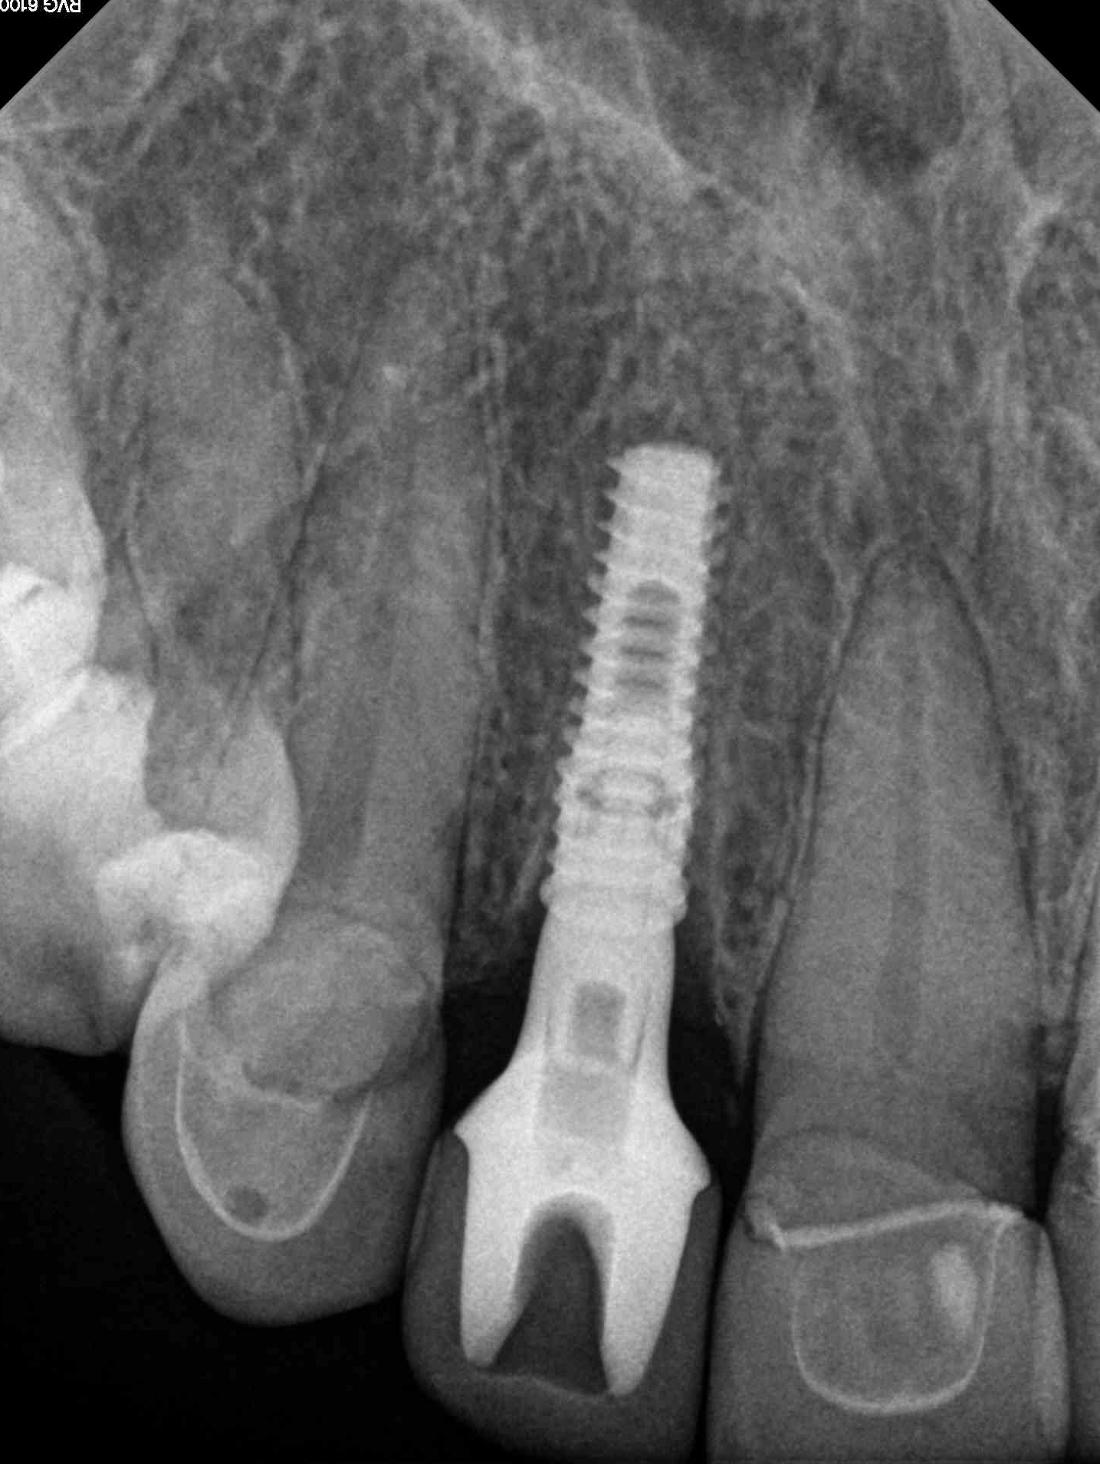

This young lady developed decay and a loose post under a crown. Unfortunately, the tooth could not be repaired and was removed. After a period of healing, a dental implant was placed by Dr. Brad Jordan. The final porcelain crown matches the crowns on her other front teeth very well.